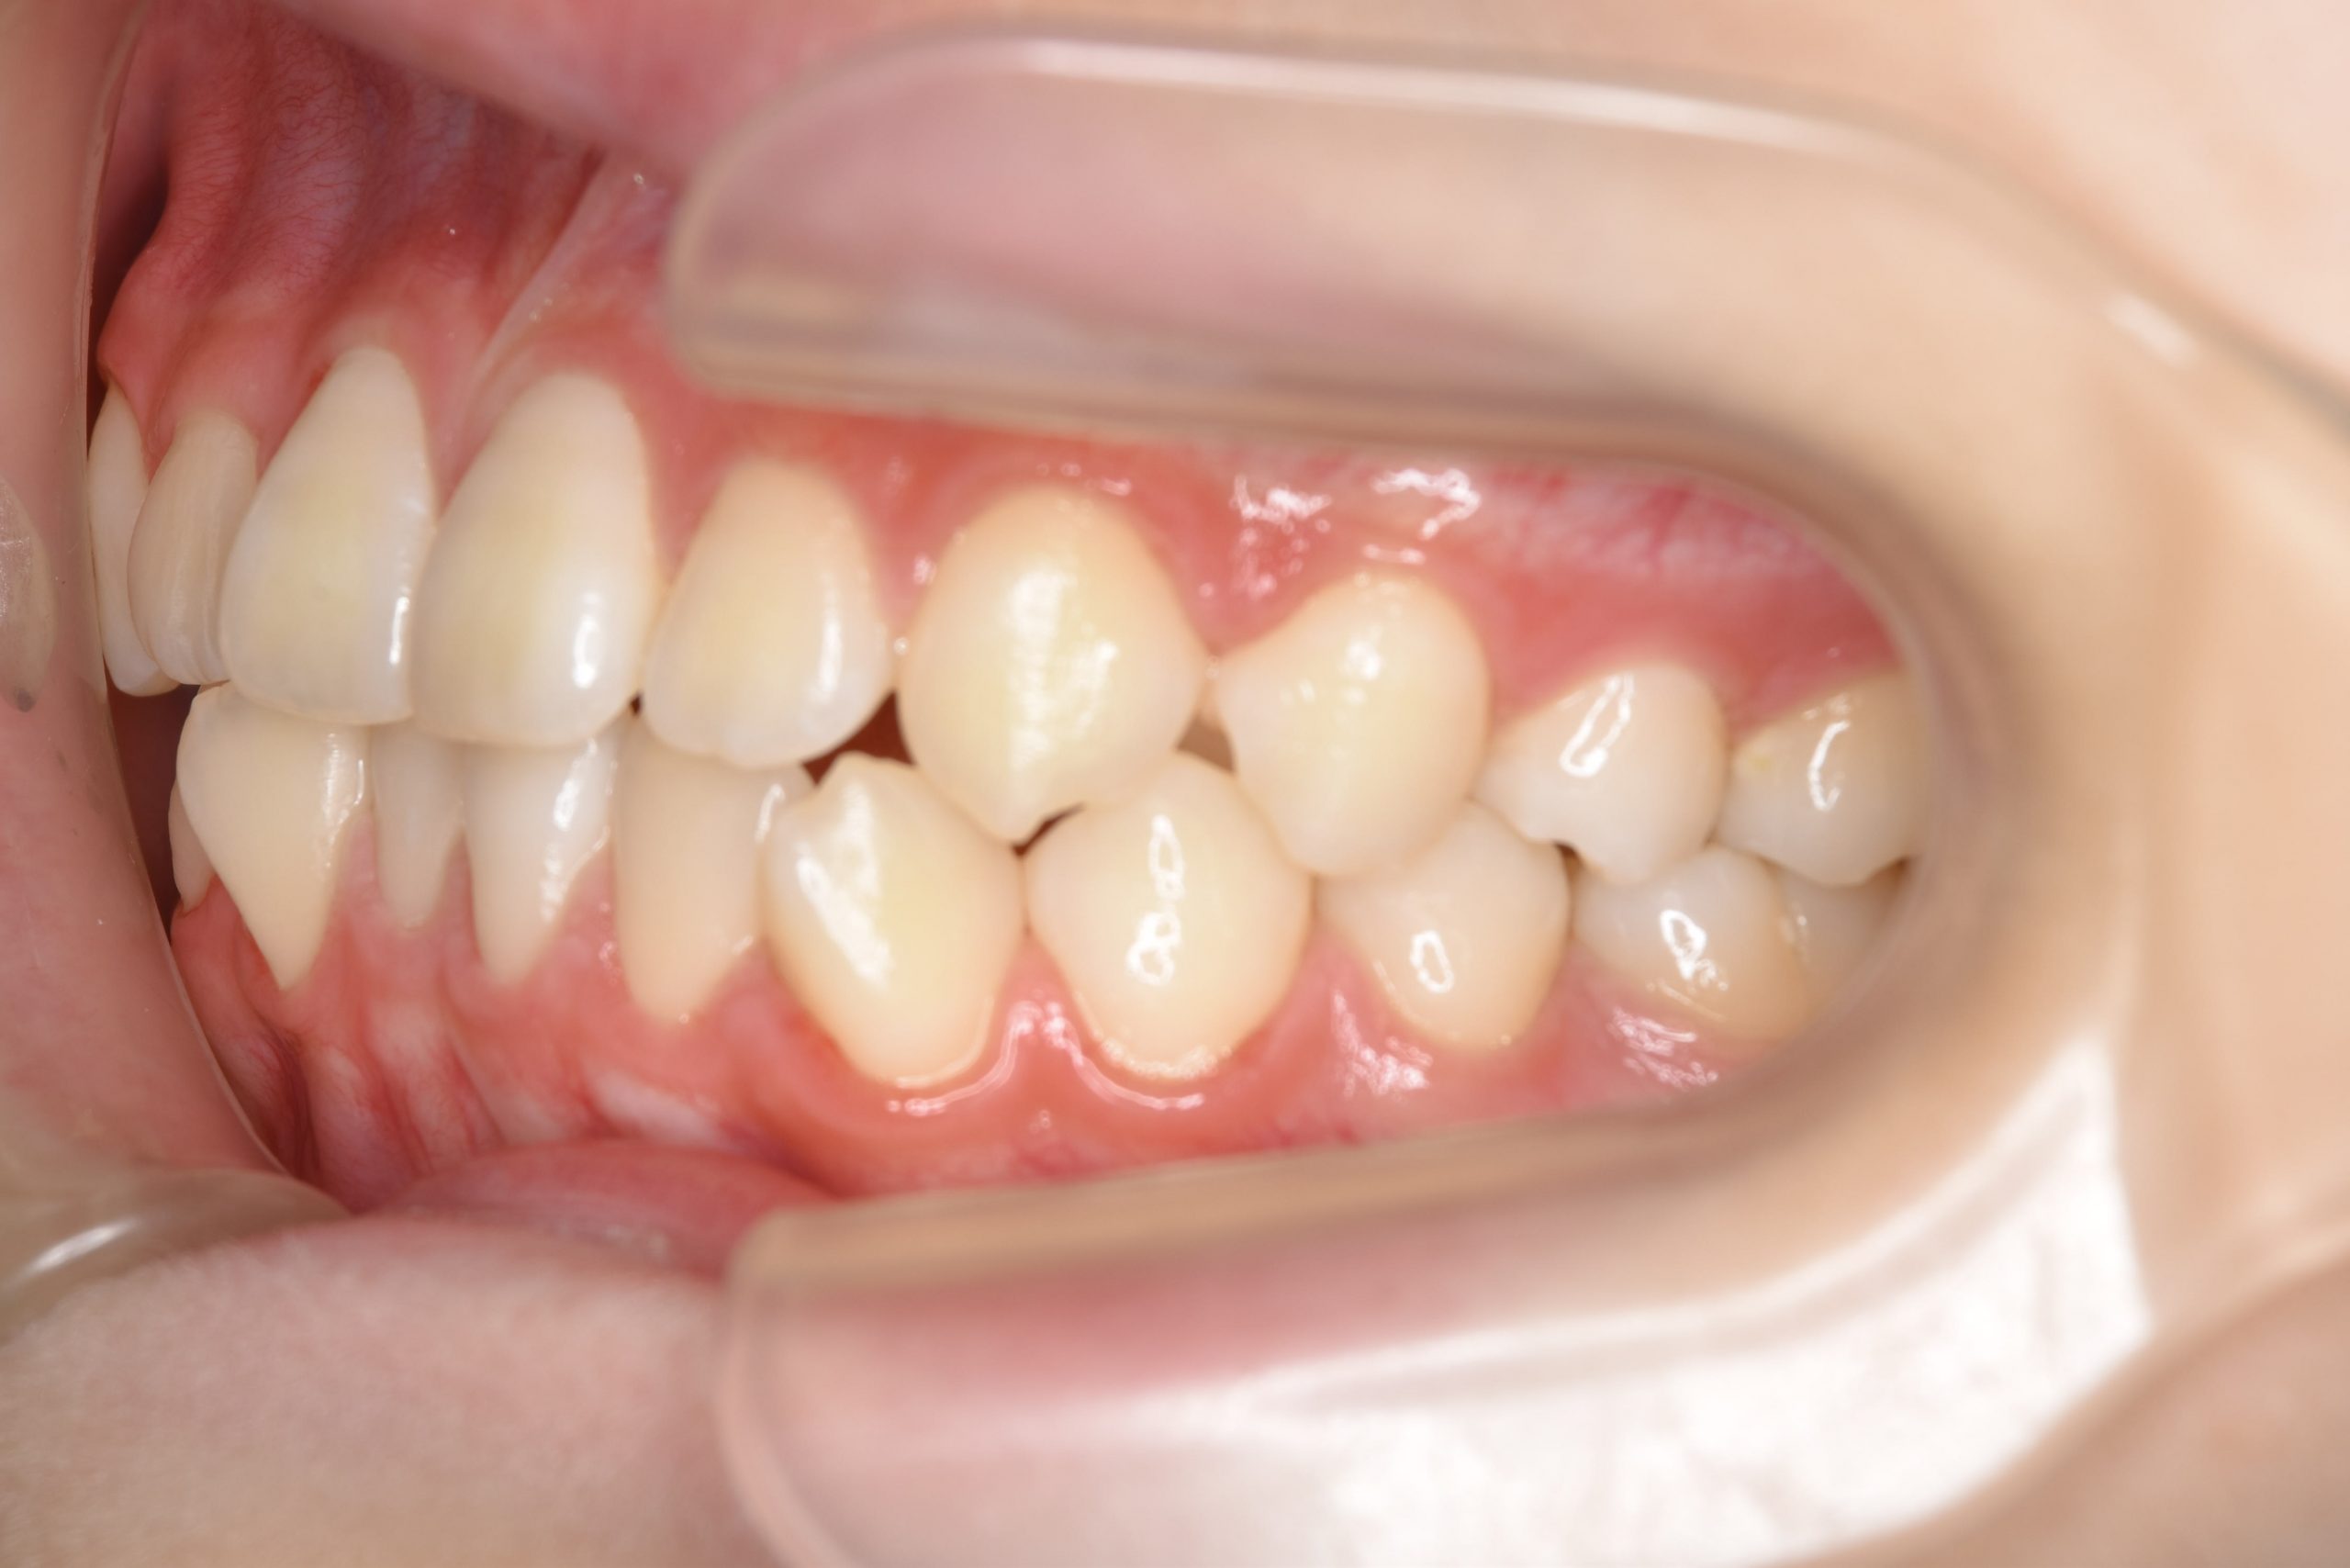

ビフォー

主訴 受け口

施術内容 上顎急速拡大装置と下顎リンガルアーチを用いて上下顎骨を拡大した。

上顎前方牽引装置を用いて上顎骨を前方に成長促進させた。

その後マウスピース型矯正装置で歯牙を配列し良好な咬合を獲得した。

治癒期間 2年9ヶ月間